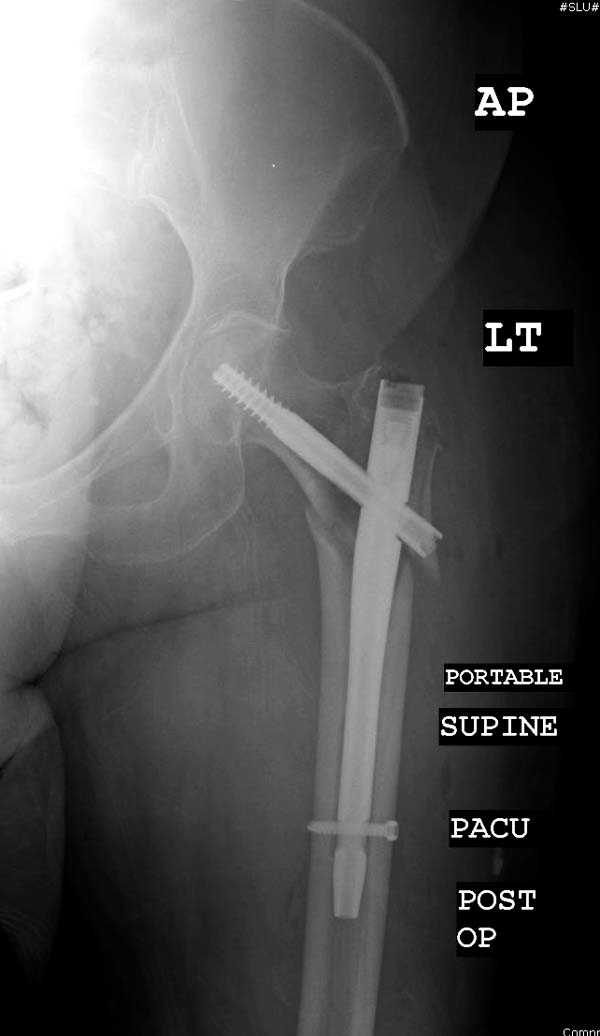

Здесь представлен случай, где в послеоперационном периоде обнаружена техническая ошибка, Gamma 3 установлен с нарушением методики. Больная в 91 лет, прооперирована через день после поступления и выписана через 48 часов.<br>

При первом послеоперационном поликлиническом осмотре больная предъявила жалобы на боли в бедре. В серийных снимках обнаружен продольный перелом верхнего отдела бедра.<br>

Считаем, что техническая ошибка произошла во время установки гвоздя, когда рассверливанию канала не уделили должного внимания. Канал остался узковат, и гвоздь был забит с силой.

Полная нагрузка конечности приостановлена на две недели, и боли в конечности изчезли. Больная начала нагрузку и перелом срастается.